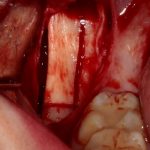

Забор костного фрагмента проводится с наружной косой линии с помощью ультразвукового пьезохирургического инструмента. Ничего сверхнового и супернеобычного тут нет, совершенно стандартная методика. С той лишь разницей, что молоток для этого используют только фашисты и только в гестапо использовать не нужно, всё делается усилием и ловкостью рук.

Нюансы начинаются с обработки принимающего ложа. Да-да, уважаемые друзья, одна из причин некроза блоков, их чрезмерной атрофии и прочих проблем — в отсутствии обработки принимающего ложа. Некоторые делают дырки, но правильнее и эффективнее поступить так:

то есть, просто снять слой кортикальной пластинки с участка, к которому будет фиксироваться костный блок. Почему? Читайте здесь>>.

Вторая особенность — мы не адаптируем и не обрабатываем костный блок invitro, а фиксируем его так, как есть:

после чего обрабатываем — доводим до окончательной формы альвеолярного гребня: